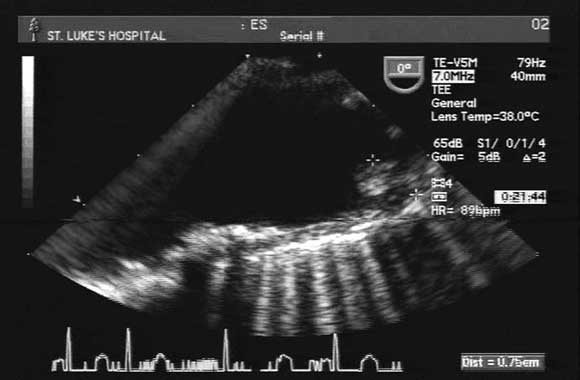

A transoesophageal echogram showed normal cardiac and valve function, with no obvious thrombi. However, there were diffuse atherosclerotic changes in the aortic arch, with a grade-IV protruding atheroma (7 mm) proximal to the innominate artery (Box). An arterial Doppler study of both upper extremities showed a lack of flow in the right ulnar artery.